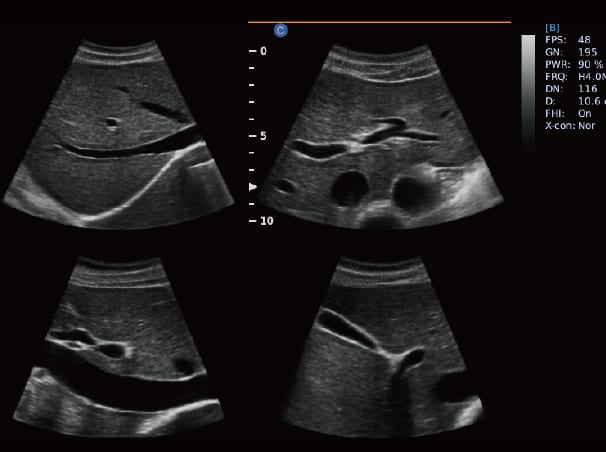

Television X-rays or sonars are an essential tool for accurately and safely diagnosing and following up on pregnancy, gynecology, and other medical conditions. Multiple types of sonar are available at Afaq Medical Care Center in Ibri, including:

• 2D radiation: The most commonly used, it shows flat images of the inside of the body, and is used to evaluate fetal growth, organ position, and diagnose conditions.

• 3D scans: Showing stereoscopic images of the fetus, used to follow up on congenital abnormalities or facial and limb details.

• 4D Rays: Allows the fetus to be seen live and directly in real time (animated video), providing a distinct emotional experience for the mother and father.